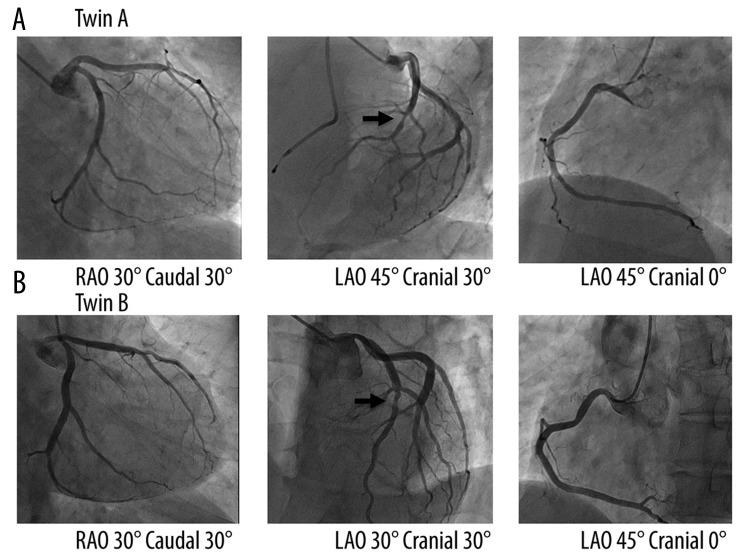

Figure 3.

Comparison of the structure of the left (left and middle panels) and right (right panel) coronary arteries between Twin A (A) and Twin B (B). The right upper (Twin A) and lower (Twin B) panels show left coronary arteries from the right anterior oblique (RAO) 30°/caudal 30° views. The middle upper (Twin A) and lower (Twin B) panels show left coronary arteries from left anterior oblique (LAO) 45° and LAO 30°/cranial 30° views, respectively. The left upper (Twin A) and lower (Twin B) panels show right coronary arteries from LAO 45° views. Comparison of coronary angiograms indicated similar structure of coronary vessels, including short left main trunk. Referring to the middle panels, coronary angiograms revealed there was 50% stenosis at the proximal portion of the left anterior descending coronary artery (indicated by an arrow), although the angles of LAO view were different.